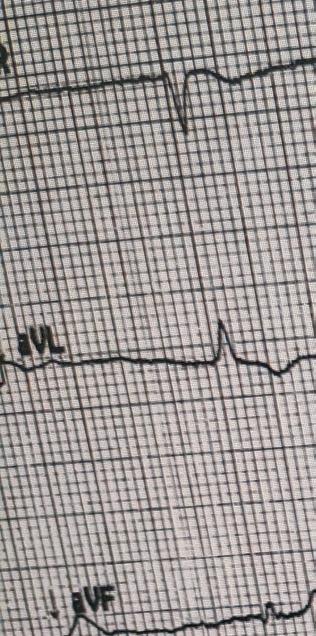

Heart attack or cardiac arrest?

What is the difference between a heart attack and cardiac arrest? A heart attack occurs when the flow of blood to the heart is severely reduced or stopped. The lack of blood flow can destroy or damage part of the heart muscle. Cardiac arrest is when the heart stops beating. It may be caused by a heart attack or other factors, such as a drug overdose or electrical shock.